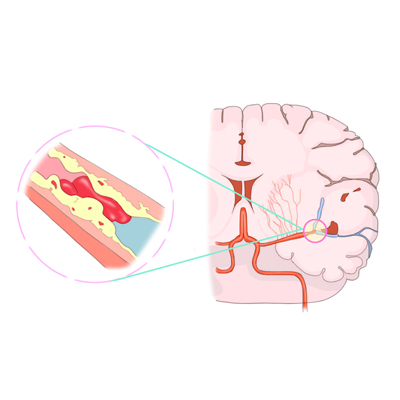

허혈성 뇌졸중으로 가장 흔한 유형의 뇌졸중입니다. 뇌의 혈관이 좁아지거나 막혀 혈류(허혈)가 심하게 감소할 때 발생합니다. 혈관이 막히거나 좁아지는 것은 혈류를 통해 이동하고 뇌의 혈관에 남아 있는 혈관에 축적되는 지방 침착물, 혈전 또는 기타 이물질로 인해 발생합니다.

경부혈전증은 경동맥 경화증은 시간이 지남에 따라 경화되어 콜레스테롤이 혈관에 축적되어 동맥의 원활한 흐름을 차단할 수 있습니다.